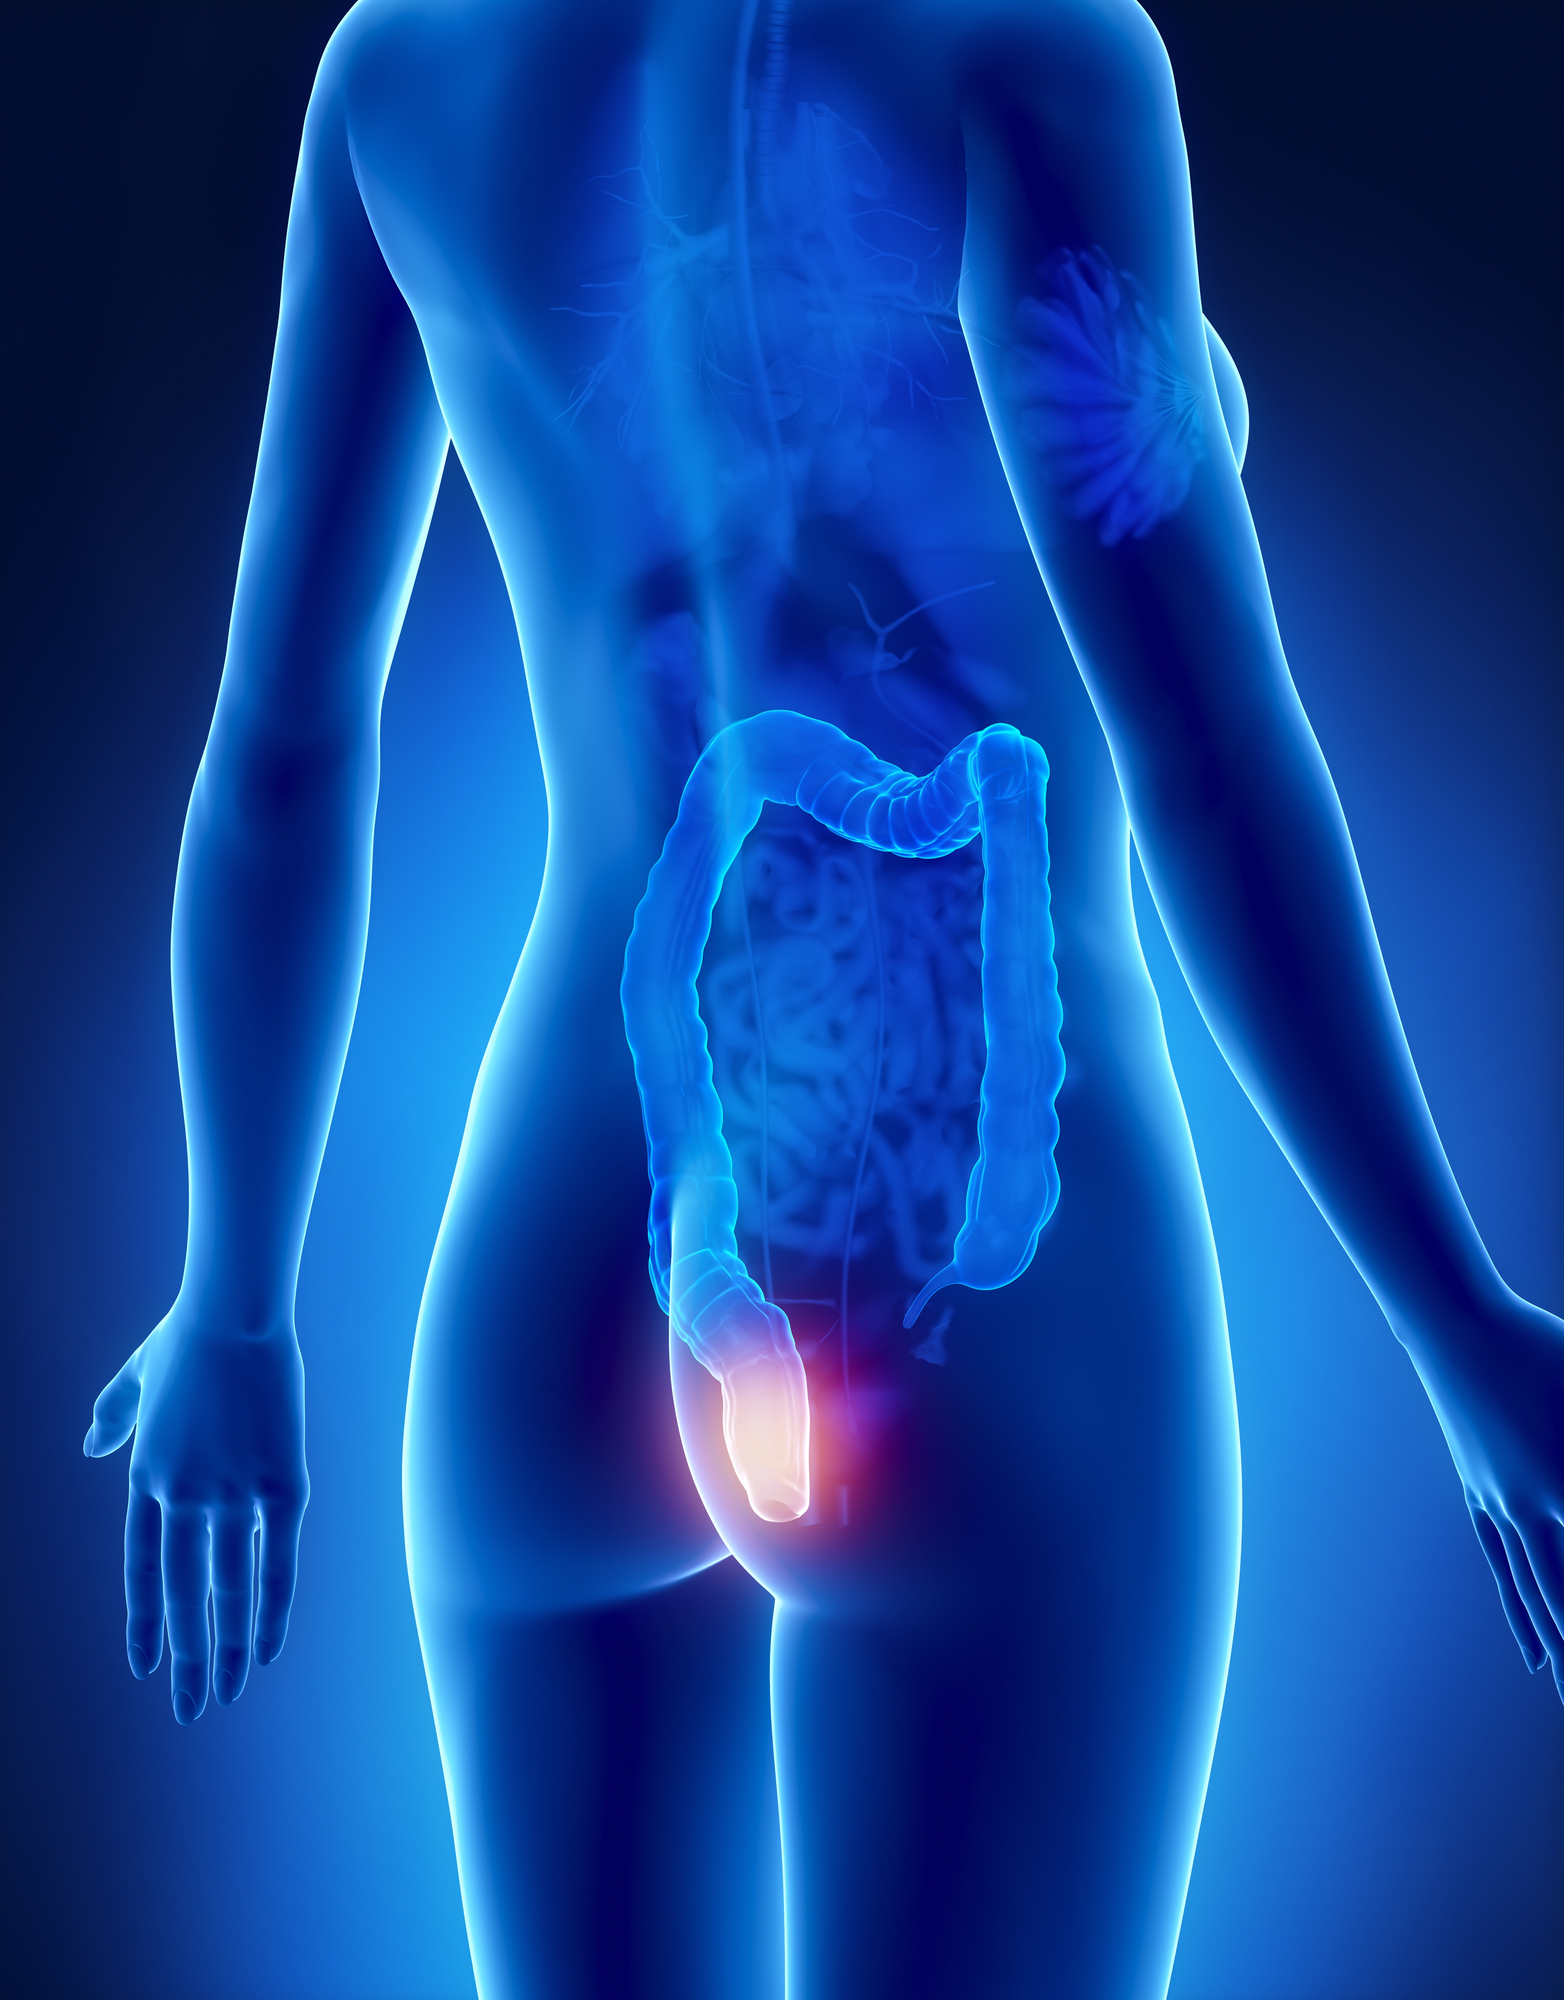

What Is Hemorrhoid Embolization? (HAE)?

Hemorrhoid Embolization, also called Hemorrhoidal Artery Embolization (HAE) or Embolization technique, is a minimally invasive, non-surgical procedure used to treat symptomatic internal hemorrhoids that cause bleeding, discomfort, or swelling.

Unlike traditional surgery, this advanced treatment works by blocking the abnormal blood flow feeding the hemorrhoidal tissue, leading to shrinkage and long-term relief, with no cutting, stitches, or general anesthesia.